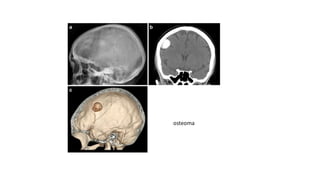

OSTEOMA

El osteoma es un tumor benigno raro de hueso, que parece tener un origen

perióstico o yuxtacortical.

Se da más a menudo en adolescentes y adultos, y tiene preferencia por el

sexo masculino.

Tipos: .- Clásico o convencional (huesos de osificación membranosa),

.- Parosteal (exostosis o hiperostosis postraumática),

.- Medular (islas óseas) y

.- Síndrome de Gardner (osteomas, poliposis colónica, tumores de

tejidos blandos. De transmisión autosómica dominante).

I. OSTEOMA

El osteoma clásico se da en el cráneo, senos paranasales y la mandíbula.

El parosteal en los huesos largos y

El medular en el tercio medio de la tibia y el fémur.

Clínica:

Los osteomas suelen ser de crecimiento lento, indoloros salvo cuando ejercen

acción mecánica sobre estructuras vecinas, pero producirán una gran masa ósea

visible y palpable. En ocasiones debuta con una sinusitis o una masa que deforma

las paredes de la órbita, o una protrusión en la mucosa bucal.

Rayos X ; La lesión es circunscrita de extraordinaria densidad, redondeada y

generalmente menor de 2 cm, aunque pueden alcanzar dimensiones enormes.